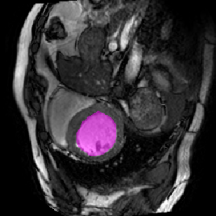

Figure 3 illustrates the specific segmentation results on the SABS dataset under Setting 1. Our model demonstrates higher accuracy in segmentation and effectively reduces unnecessary segmentation. Even under Setting 2, where the test class is entirely invisible to the model, our model performs well, as depicted in Figure 4. Given that SABS is a multi-organ dataset with many organs of small size, precise segmentation proves challenging. However, our model excels, particularly in the scenario of completely invisible classes, which closely resembles real-world conditions. Figure 4 highlights our model’s ability to accurately segment very small target organs, such as the right kidney. In contrast, the ADNet method fails to produce effective segmentation predictions, and other methods exhibit varying degrees of over-segmentation. On the CMR dataset, as shown in Table 2, our model generally outperforms others.